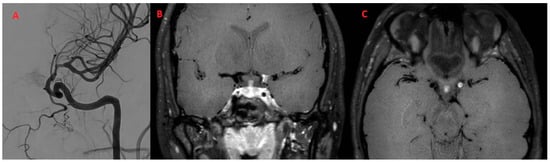

| 49y, M | Headache, hearing disorders | Positive (inflammatory pattern + T. Pallidum positivity) proteins 82 (nv < 50), WBC 73 (nv < 5), TPHA liquor + 1:640 | Negative | T. Pallidum antibody-positive (TPHA > 1:640, RPR +) | (n/a) | Luetic CNSV |

| 58Y, M | Episode suggestive of stroke | Positive (inflammatory pattern + T. Pallidum positivity) proteins 103 (nv < 50), WBC 17 (nv < 5), TPHA liquor + 1:640 | Negative | CRP (+), T. Pallidum antibody-positive CRP 1,7 (nv < 0.5), ESR 52 (nv < 20), T. Pallidum antibody-positive (TPHA 1:640, RPR +) | Large-vessel uptake | Luetic CNSV |

| 49Y, M | 1 | Present | Present | Multiple subcortical in MCA territories | ICA | MCA (M1) ACA (A1) | Present | Subtentorial |

| 58Y, M | 2 | Present | Present | Multiple subcortical in ACA and MCA territories and left SCA | ICA | None | Present | Supratentorial |